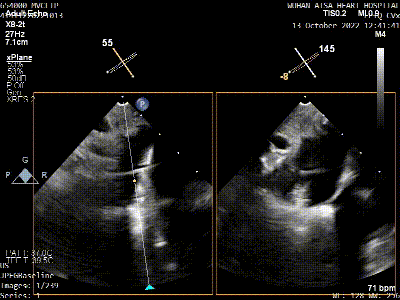

术前TEE评估

原发性二尖瓣反流(DMR),后叶P3区脱垂,反流程度4+,EROA 0.40cm2、RV 39ml;二尖瓣瓣口面积5.37cm²;二尖瓣前叶(A3)长度14.0mm,二尖瓣后叶长度(P3)长度12.2mm,脱垂宽度8.2mm,脱垂高度1.4mm;RA 2.9cm ,LA 3.6cm,左室射血分数LVEF56%,术前测量最大房间隔穿刺高度4.0cm